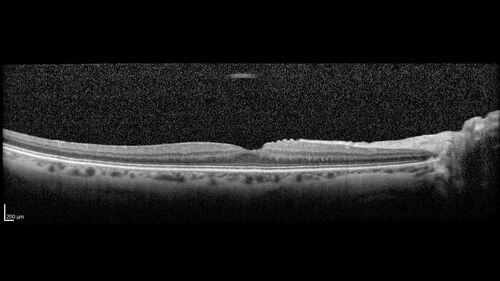

Central Retinal Vein Occlusion with cilioretinal artery occlusion

63 year old female who lost vision in the left eye 2 days ago. She was in the emergency room and had a lot of tests done which were all reportedly normal. The right eye is OK.

VA OD: Dcc20/25 NccJ2

VA OS: Dcc20/200-1 PHNI Ncc20/400-1

IOP: TP: OD:11 OS:12